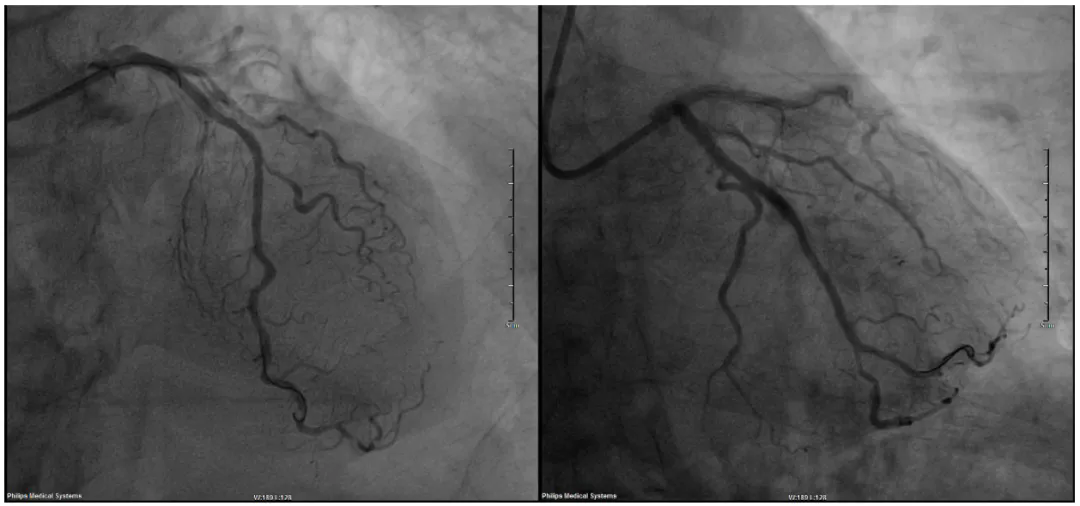

支架植入术后造影显示血流通畅

60岁的李先生有多年高血压和糖尿病史,近期反复出现胸痛症状,冠脉CTA显示其冠状动脉存在严重钙化并累及三支血管。经我院心内科团队全面评估,决定采用冠脉造影明确病变程度后,实施斑块旋磨技术联合支架植入术。术后患者症状消失,恢复良好。

钙化病变往往提示严重冠脉病变,为应对这一难题,我院心内科团队常规开展包括切割球囊扩张、冠脉斑块旋磨技术。斑块旋磨技术是采用橄榄形的带有钻石颗粒的旋磨头,像精密打磨机一样将坚硬的钙化斑块粉碎,同时正常血管组织因其弹性而自动避开,通过旋磨处理后,血管变得柔软通畅,为后续球囊扩张和支架植入创造理想条件,手术过程更顺利,还能显著降低支架贴壁不良、再狭窄等并发症风险。